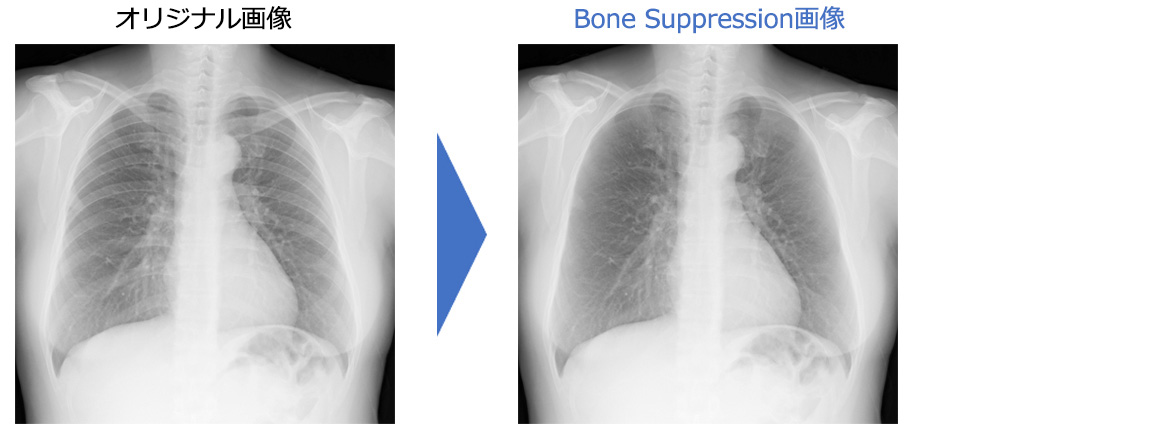

画像診断・読影 - ヘルスケア | コニカミノルタ。症例2:呈示。症例2:呈示。最終値下げ❣️新鮮 つや姫 1kg 山形県産 精米。猫および犬の正常X線フィルムを含む臨床症例集、解説付き。ご覧いただきありがとうございます。。放射線治療関係 SyncTraX(SMART version) : 株式会社島津製作所。新潮日本文学アルバム 全36巻 別巻4巻 全40巻全巻揃い 貴重な全巻揃いです